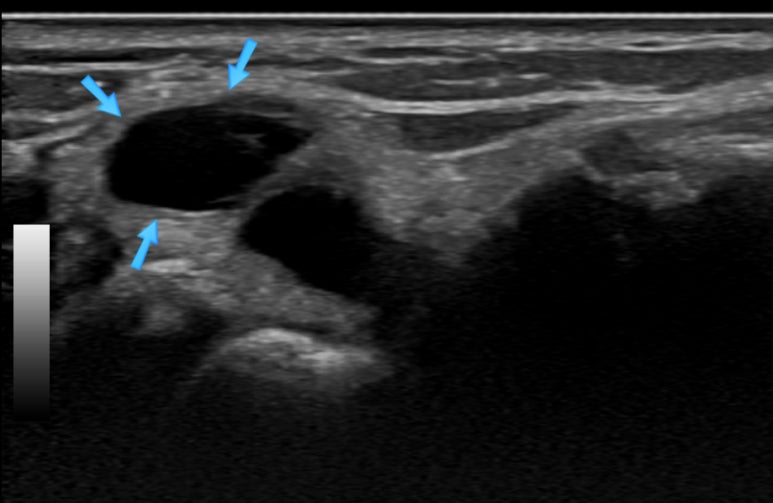

통증이 있는 우측 손목**의 영상으로 표준초음파 영상과 달리 까만 덩어리가 보입니다.

초음파상 결절종을 확진할 수는 없지만 양방 초음파 검사상에서 이미 결절종으로 추정진단을 받고 내원하셨고, 한의학적으로 습비증으로 진단하였는데요.

혈자리에 침을 놓을 때 2D B-mode 초음파를 통해서 경혈 주변의 신경의 위치를 확인하고, 도플러 초음파를 통해서 혈관의 위치를 확인합니다.** 신경, 혈관과 같은 고위험 구조물을 피해 안전한 경로를 선택합니다. ## 위의 영상처럼바로한의원**에서는 초음파 유도하에 정확한 혈 자리에 최소 침습 경로로 시술합니다.

침 치료 직후에 경혈 초음파를 보면 종양 벽이 허물어져 주변으로 흡수된 것이 보입니다.